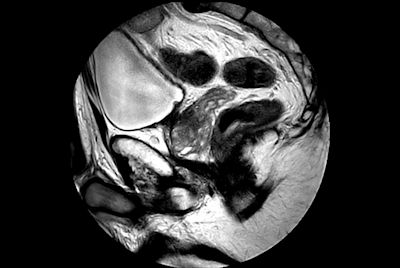

mDIXON XD TSE - Ankle tumor